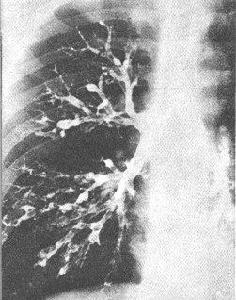

图片题 下列属于图中典型临床表现的是( )

A 慢性咳嗽,黏液或泡沫状痰,气急

B 反复高热,慢性咳嗽,咳白色泡沫痰

C 低热,刺激性咳嗽,黄脓性痰

D 慢性咳嗽,大量脓痰,反复咯血

E 低热,慢性咳嗽,咳大量脓血痰

正确答案

D